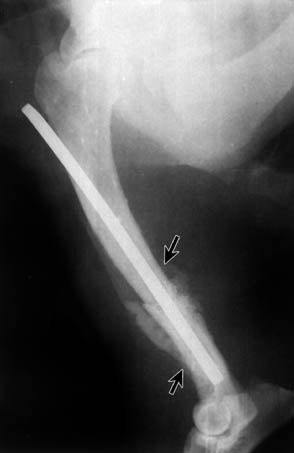

Between weeks 2 and 4, twenty dogs (90%) radiologically presented an irregular-shaped periosteal reaction with new bone formation (Fig. 1). A characteristic feature was that this occurred far from the fracture site, along the bone. In some cases, there were spicule-like formations with denser shadows (Figs. 2 and 5). In the event that a fragment of a comminuted fracture became necrotic, that is, that it turned into a primary sequestrum, it was surrounded by a dense shadow - a product of the periosteum (Fig. 3). During the development of osteomyelitis we observed a loosening of fixation implants in 15 dogs (68%). On radiographs, the condition was seen as zones of radiolucency around the implants, and after destabilisation of fractures - there was a formation of a callus in the place of mobility without healing (Fig. 4).

Fig. 1. Lateral radiograph of the humerus in patient 33/02.11.93, two weeks after osteosynthesis. The arrows show an irregular-shaped periosteal reaction.

Fig. 2. Lateral radiograph of the humerus in patient 33/02.11.93, three weeks after osteosynthesis. The arrows show spicule-like formations - a product of the periosteum.

The radiological studies were performed over a long period of time (up to 4 months). The characteristic features in almost every sick animal were that, together with osteolysis, a periosteal reaction developed. In the beginning, the periosteum became elevated due to the exudate (Figs. 1 and 2) which exited through the Haversian and Folkmann channels.